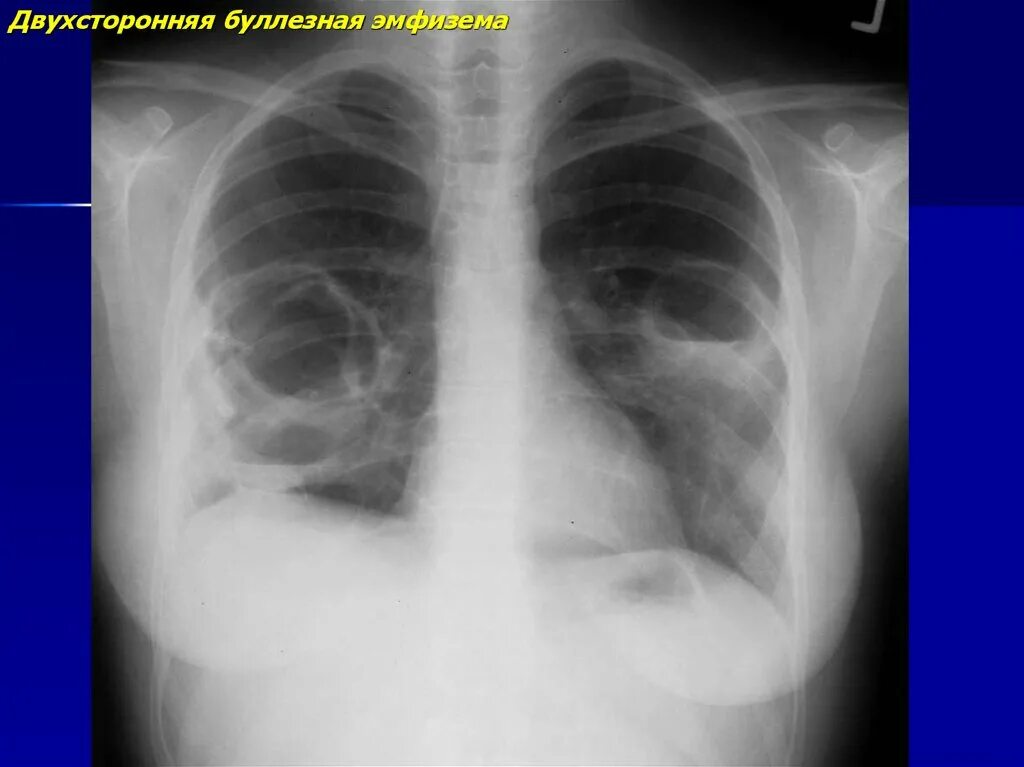

Буллезные изменения в легких